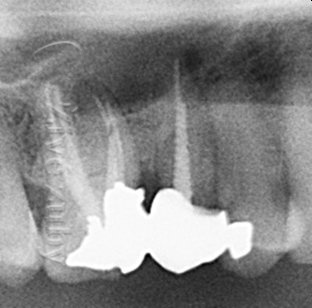

„Ošetření na jistotu“ spočívá v endodontickém ošetření, které je provedeno z důvodu hlubokého kazu. Zvýšené riziko zánětu a nekrózy zubního nervu by mohlo představovat nepříjemnou zkušenost pacienta. V té době bylo doporučováno „zpevňovat zuby“ kovovými čepy a zhotovit zubní korunky s poměrně výraznou preparací. Odhadovaná cena ošetření je cca 10 000Kč. Z dnešního pohledu se jedná o ne zcela vhodné postupy, které vedly k předčasnému selhání práce a extrakci zubu. Záložní plán spočívá v zavedení zubního implantátu, cca 30 000Kč.